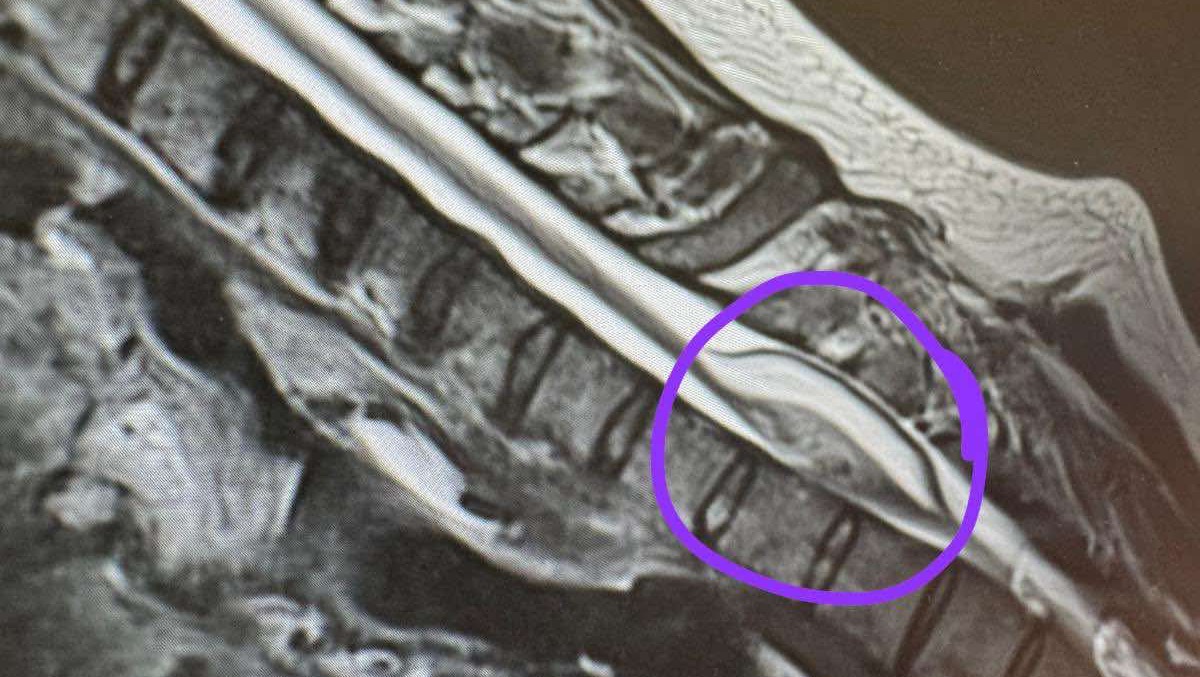

Image showing the tumor inside of the spinal cord (T2)

In May 2025, Simon’s life changed forever. What was meant to be a hopeful surgery to remove a rare tumor from his spinal cord has left him paralysed from the chest down.